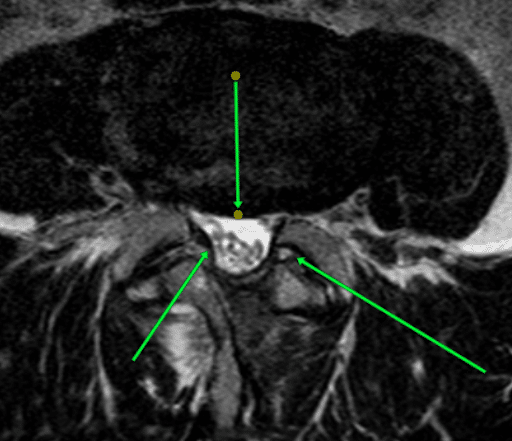

Stan po leczeniu operacyjnym

Strzałki wskazują poszerzone brzegi kanału kręgowego. Średnica kanału została zwiększona. Teraz widać pojedyncze korzenie nerwowe oraz biały płyn mózgowo-rdzeniowy.